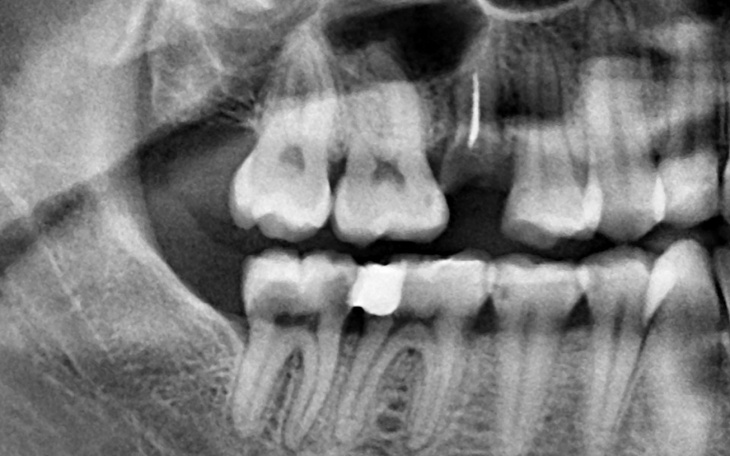

5 ząb dolny po lewej stronie i prawy ząb dolny po prawej stronie - te dwa zęby to nie tylko ból, ale i strach przed utratą. Dominika nie chce tracić ich w tak młodym wieku, zwłaszcza że jeden z nich już się wykruszył, pozostawiając jedynie korzeń.

Zdjęcie było wykonane w lutym i od tamtego czasu stan się pogorszył...